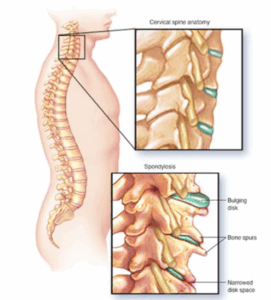

Spondylosis ,cervical

Cervical spondylosis is a general term for age-related wear and tear affecting the spinal disks in your neck. As the disks dehydrate and shrink, signs of osteoarthritis develop, including bony projections along the edges of bones, known as bone spurs.